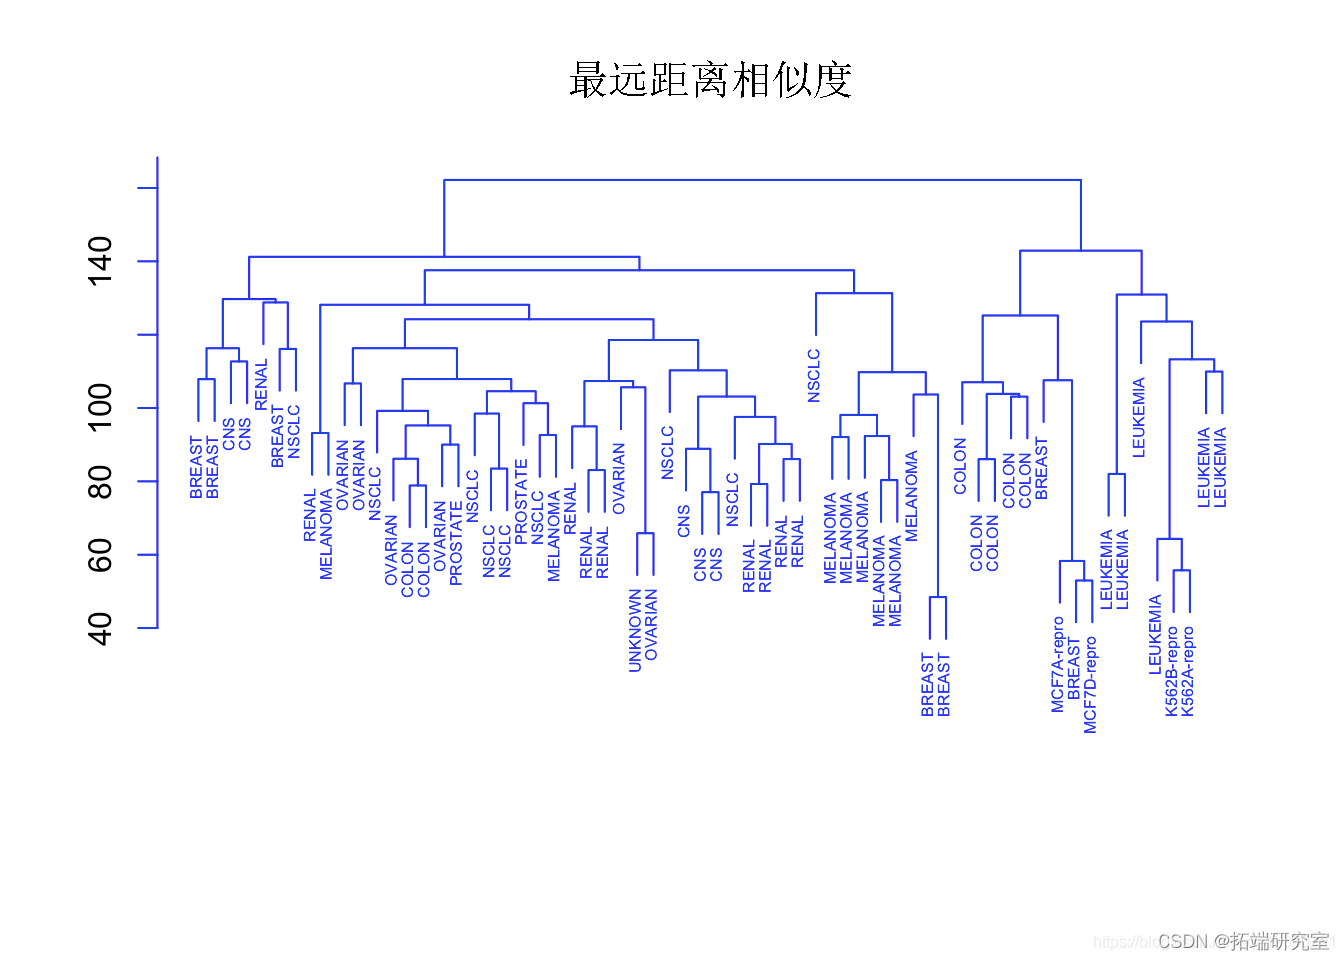

scale # 标准化变量(均值零和标准差一)。全链接、平均链接和单链接之间的比较。

plot(hclust,ylab = "",cex=".5",col="blue") #使用全链接对观察结果进行层次聚类。

观察结果

单链接聚类倾向于产生拖尾的聚类:非常大的聚类,单个观测值一个接一个地附在其中。

另一方面,全链接和平均链接往往会产生更加平衡和有吸引力的聚类。

由于这个原因,全链接和平均链接比单链接层次聚类更受欢迎。单一癌症类型中的细胞系确实倾向于聚在一起,尽管聚类并不完美。